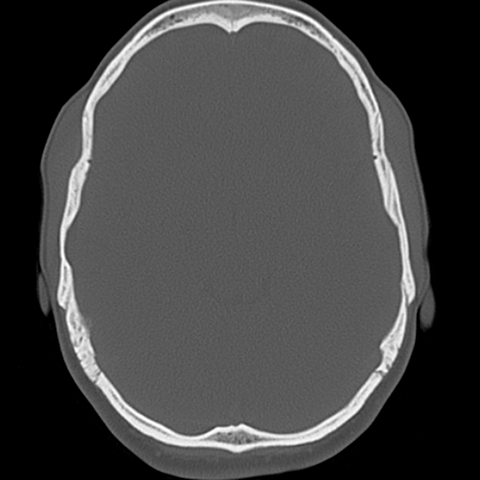

Lower calvarial vault [4 of 7]